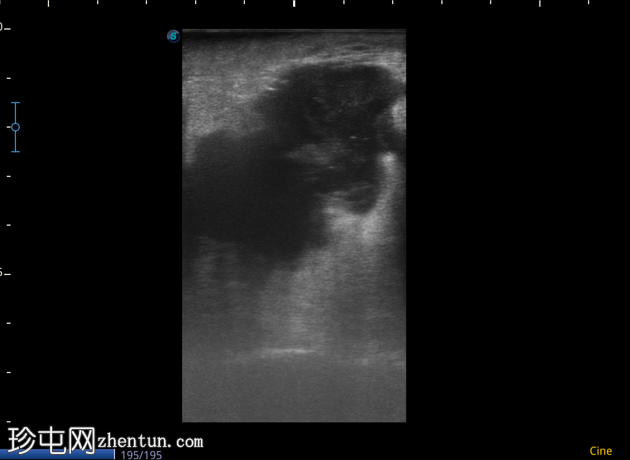

4-10点钟平面

浅表探头

在右前外侧肛周区域(具体位置为10-11点钟方向,紧邻肛壁)观察到一个边界清晰、大小约为5 x 5厘米的低回声病变。病变壁不规则,后部回声增强。病变内部回声提示可能存在肛周脓肿。

在此阶段,未见内部瘘管或与肛管的交通。此外,未检测到明显的病灶周围血管或气体灶。为了更好地评估病变的定位和范围,除了浅表探头外,可能还需要深层探头。